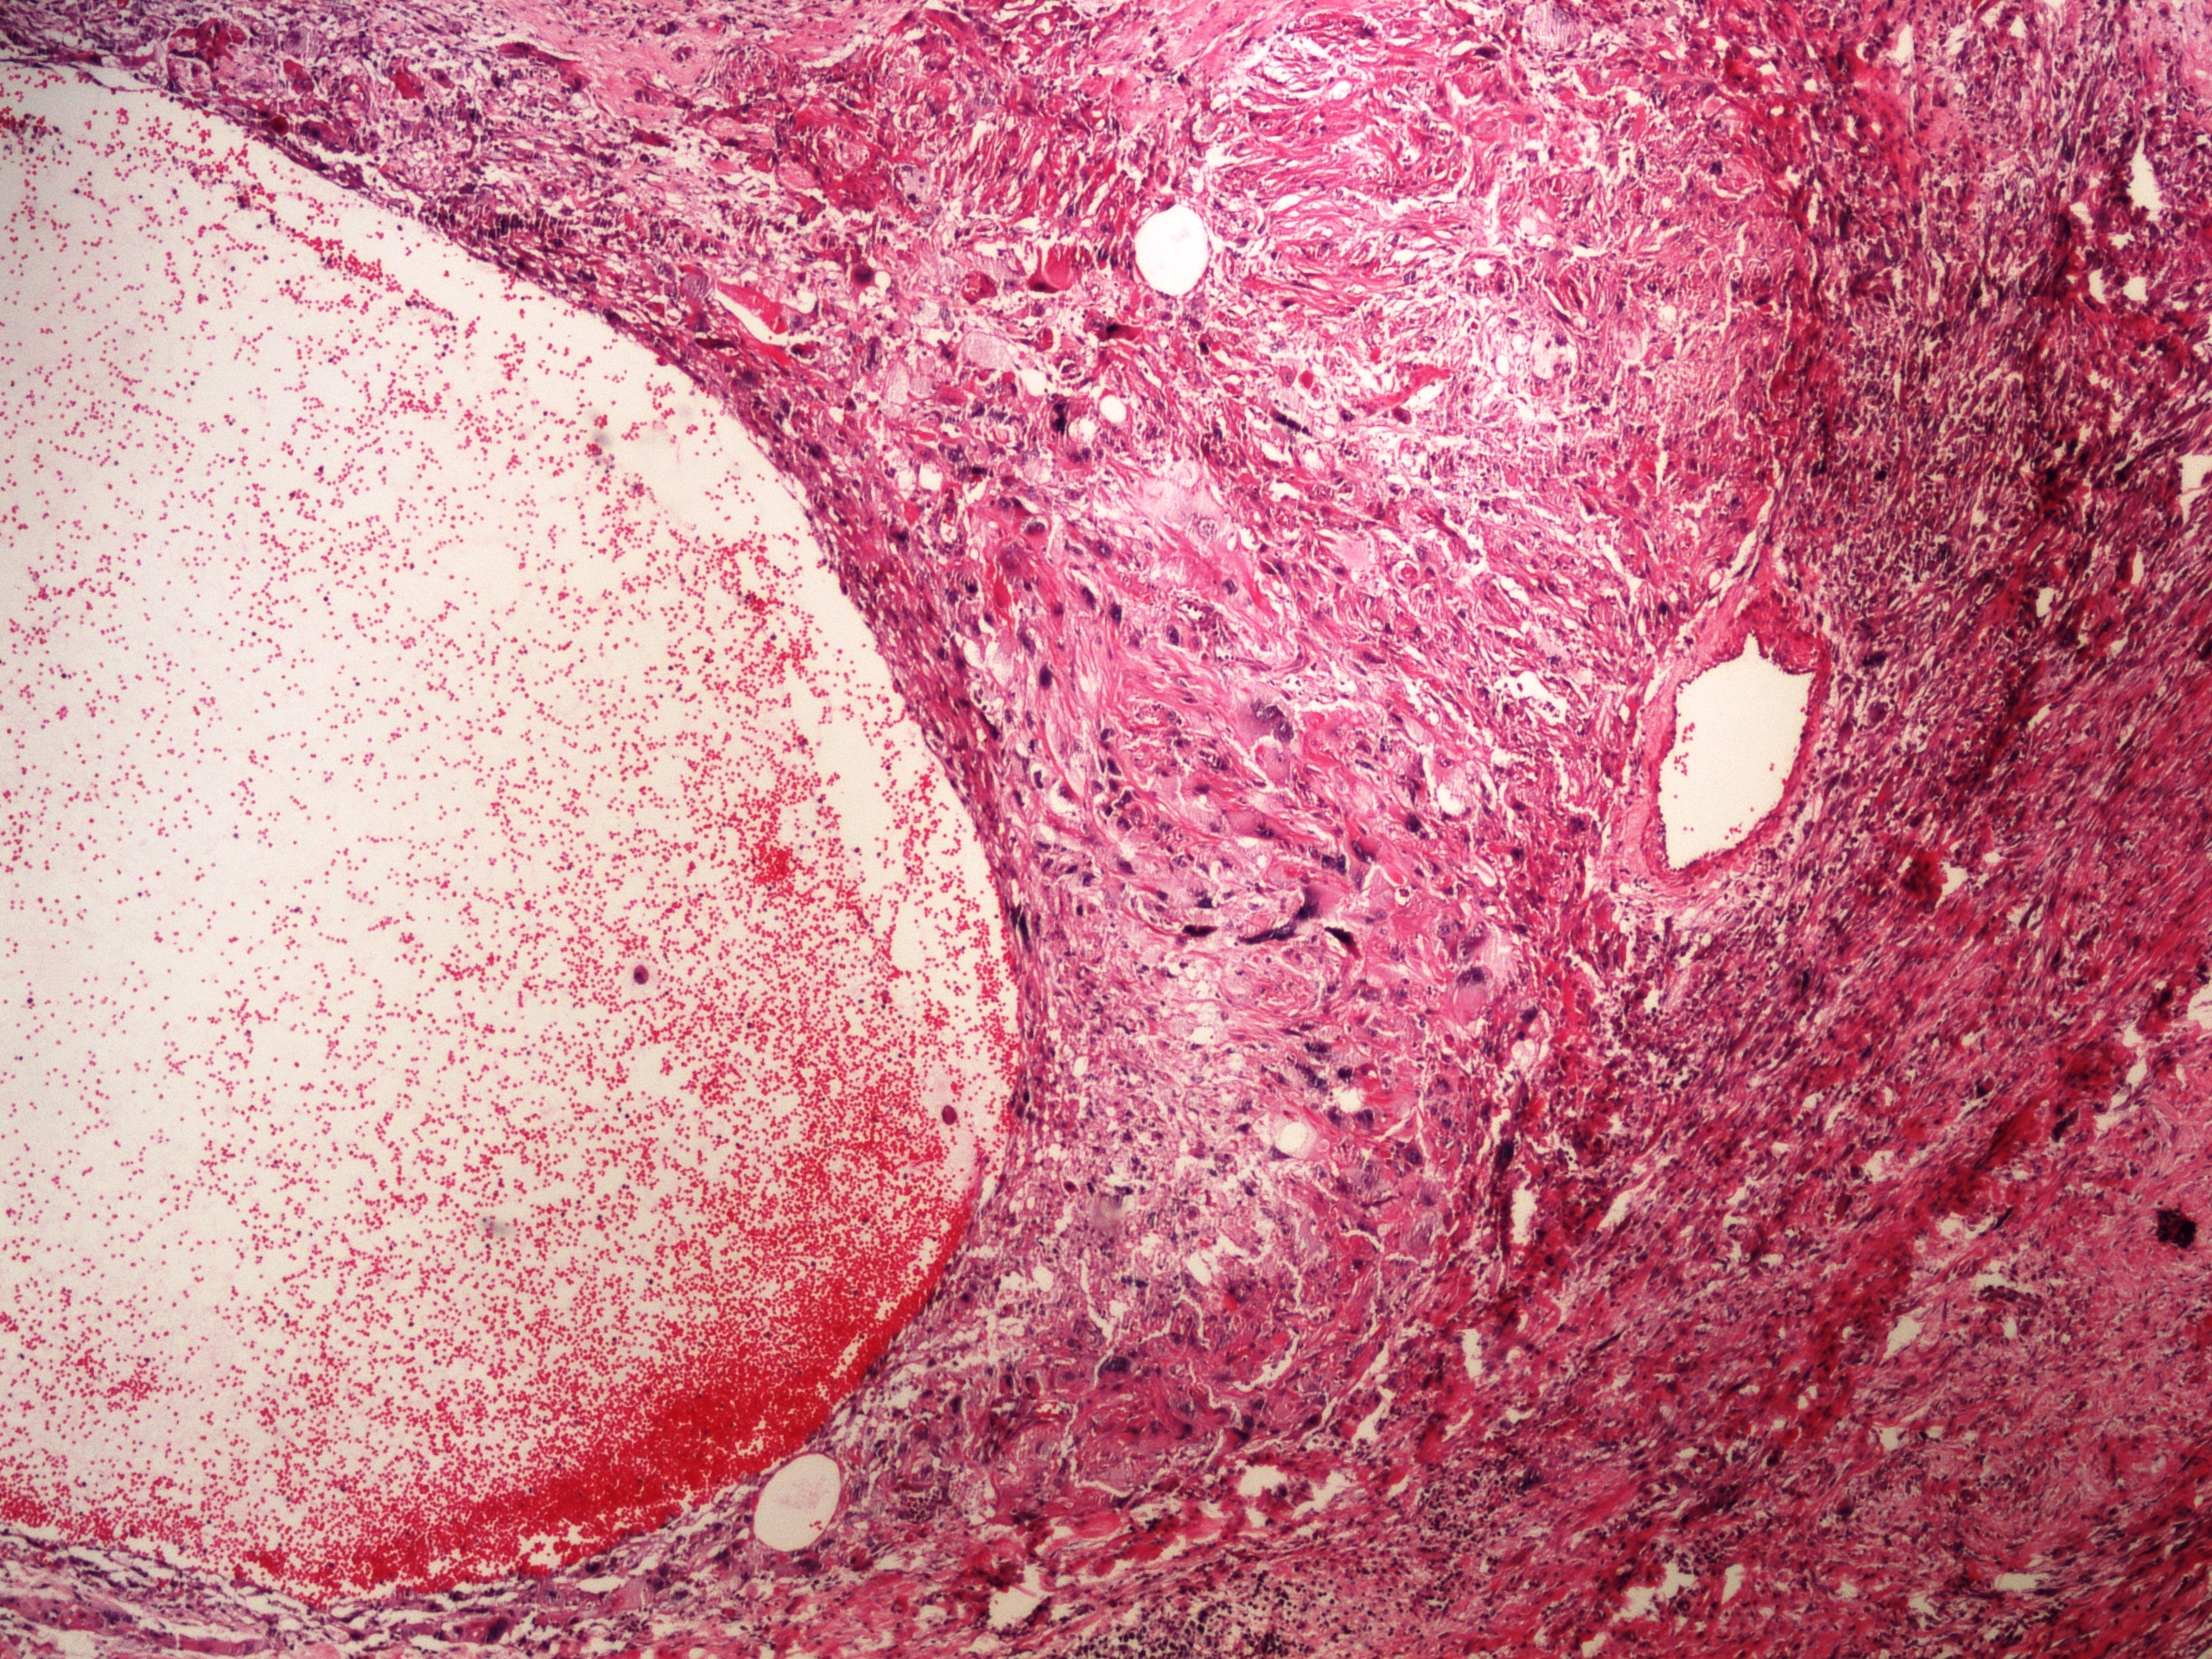

Preparát č.1 a č.2 - kavernósní hemangiom jater

Struktury

- hemangiom

- jaterní parenchym

- blandní epitelie - stěna hemangiomu